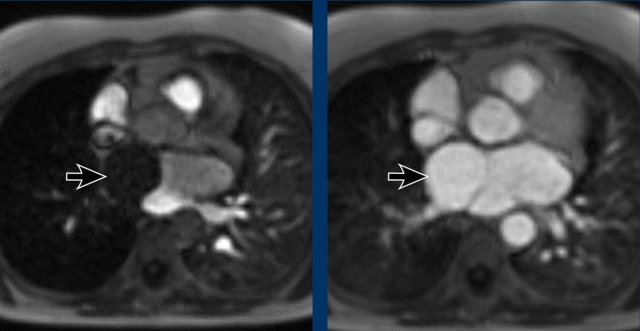

Here the MR of the same case

Images

Delayed filling of the right compartment of the left atrium in a cor triatriatum sinistra.